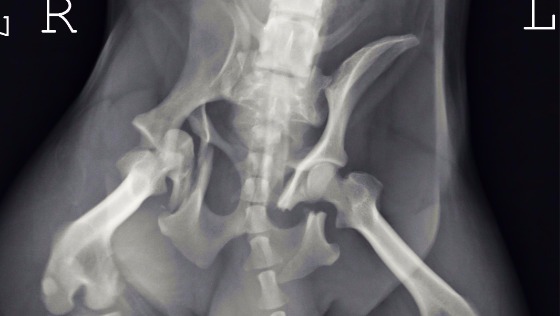

Po konsultacjach z weterynarzem konieczna jest operacja rekonstrukcji obustronnie połamanej miednicy i kości. Zmiażdżona jest też panewka stawu biodrowego. Połamane kości utrudniają wypróżnianie bo uciskają na jelita psa,. Nerwy nie są na szczęście uszkodzone. Nie może chodzić. Konieczne są środki przeciwbólowe.